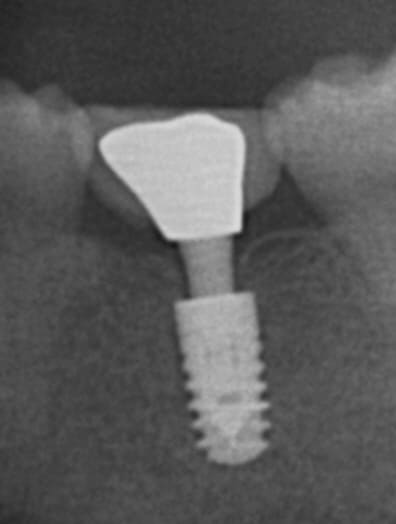

implant mis en charge il y a 3 ans

ANKYLOS sous crestal, piler standard

C'est le plus sous crestal que j'ai vue

Flic, flac : rien de particulier car pilier avec limite juxtagingivale

En fait pas de comblement, pose à 2 mois post extraction

très beau le platform switching...